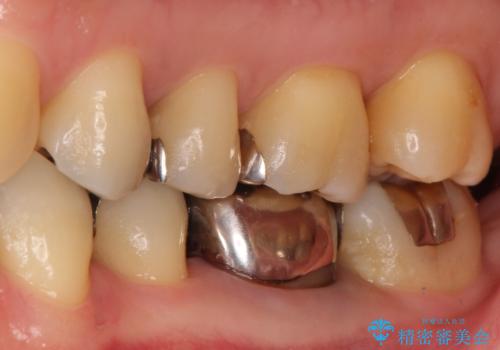

- 金属を外して白い歯を手に入れたいとのことで来院されました。

まとめて治療することで通院回数を減らすことができ、見た目も大変満足していただきました。

根管治療歯は破折防止のため速やかに被せ物が必要になります。